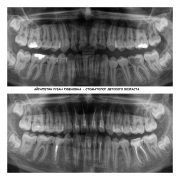

Уже не первый год ходим к Рузан Рубеновне, это лучший врач! Как по качеству лечения, так и по отношению к детям. Сейчас пришли с болью в зубе, выбрали план лечения. Сделали снимок. Всегда все по полочкам разложит врач и расскажет, но останется ни одного вопроса. Благодарю за такое отношение однозначно, рекомендую к посещению другим детям. Будем дальше посещать и сами

Доктора Айрапетян порекомендовала сестра, была здесь с двумя детьми. Я привела сюда дочь, она боится лечения, боли. Доктор расположила к себе ребенка, сделали снимок, все рассказали. После первых манипуляций дочь занервничала, и совместно с врачом приняли решение лечить под общим наркозом. Оперативно нашли время для записи. Доктор быстро нашел подход к ребенку и разъяснил подробно фронт работы.

- Стаж работы более 7 лет, Более 750 довольных пациентов только за 2018 год. Проводит лечение в наркозе. Обладает большим опытом в работе с детьми от 0 до 18 лет. В кабинете доктора ребенок будет окружен вниманием и заботой.